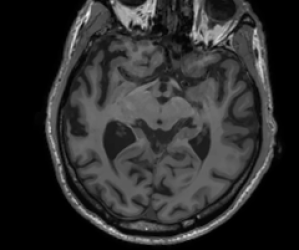

Refer to caption sinogram datafg

Refer to caption deformed ground truthfg Refer to caption deformed ground truthfg

Refer to caption side informationfg Refer to caption side informationfg

Refer to caption ground truthfg Refer to caption ground truthfg

Figure 5: PET reconstructions with structural MR side information. Filtered back-projection (FBP) and TVTV\operatorname{TV} do not correct motion and yield poor reconstructions. Both the three-step and the proposed method correct the deformation and the reconstruction satisfyingly agrees with the ground truth. We give SSIM and RD values of the reconstructed images and deformation parameters. For FBP and TVTV\operatorname{TV} no deformation was corrected and SSIM is given with respect to the deformed ground truth.

In this experiment we consider PET-MR, where we aim to reconstruct a tracer distribution using a fully sampled T1-weighted MR image of size 144×144144144144\times 144 as side information. The forward operator is modelled by a parallel beam X-ray transform with 200 angles equispaced in (0,π]0𝜋(0,\pi] and 192 bins. The sinogram data were simulated using a ground truth image deformed with respect to the side information through the rigid deformation

ϕrigid(x)=Rθx+b,subscriptitalic-ϕrigid𝑥subscript𝑅𝜃𝑥𝑏\displaystyle\phi_{\texttt{rigid}}(x)=R_{\theta}x+b, (23)

where Rθsubscript𝑅𝜃R_{\theta} is a rotation matrix (12) with angle θ=0.15.7𝜃0.1superscript5.7\theta=0.1\approx 5.7^{\circ} and b=(0.02,0.08)T𝑏superscript0.020.08𝑇b=(0.02,0.08)^{T} is a translation vector.

In this experiment we simulate data based on a dTVdTV\operatorname{dTV}-regularized reconstruction of clinical data, see [28]. The data is an instance of a Poisson random variable with parameter Ax+r𝐴𝑥𝑟Ax+r, where the background r𝑟r is chosen as constant 7 and the forward operator is scaled to about 1.31061.3superscript1061.3\cdot 10^{6} expected counts in the data. Correspondingly, the data fidelity used is the Kullback–Leibler distance (4).

The sinogram data and the deformed image which was used to generate the data are shown in the top row of Figure 5. Furthermore, we show the side information and the ground truth image. In the second row of Figure 5 we show four different reconstructions: the first one obtained through filtered back-projection, the second one utilizing TVTV\operatorname{TV} regularization, the third one using the three-step method (22), and the fourth one being the proposed method. The first two methods, which do not use the side information or correct any motion, exhibit poor image quality due to strong noise in the sinogram. On the other hand, both the three-step and the proposed method correct the deformation and the reconstructions are in very good agreement with the ground truth image.

Quantitatively, the SSIM values for filtered back-projection and TVTV\operatorname{TV} are relatively low whereas they are comparably high for both the three-step and the proposed method, with slightly better values for the proposed method. The same is also true for the relative errors of the computed deformation fields.